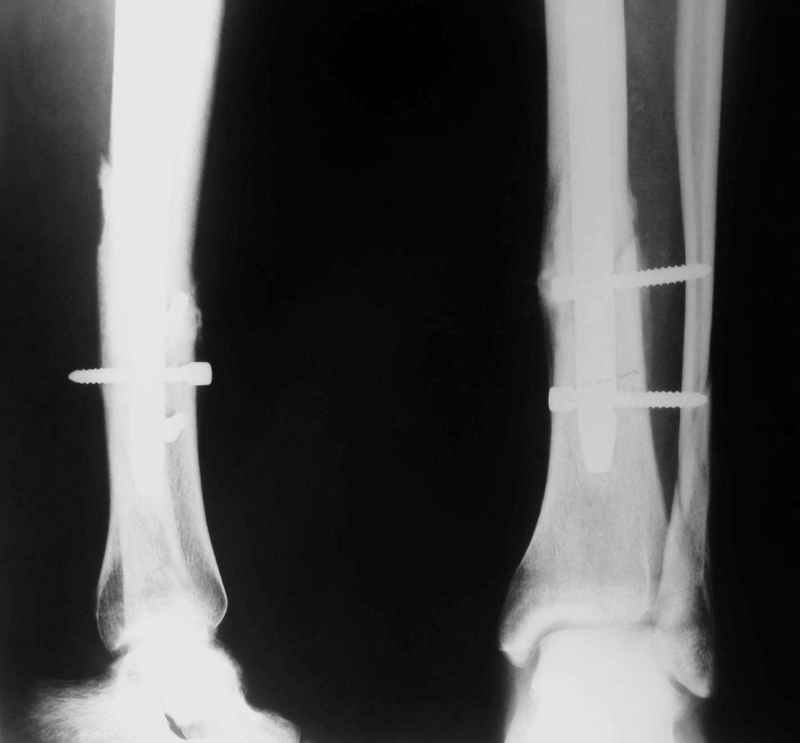

Рентгенограмы

Не удается отправить первичные снимки. А что скажите по имеющимся?!

Выполненный остосинтез нестабилен. Штифт надо заменить по "размеру" на солидный, дистльно три запирающих винта. Успехов!

Перелом спиральный, то есть низкоэнергетический, так что со сращением дело обстоит уже неплохо, лишь бы "костоеда" не развилась. Отломки выглядят уже стабилизированными костной мозолью, так что довводить винты, наверно, уже незачем. Разве что при клинической оценке подвижность еще есть - тогда можно для стабилизации наложить простейший аппарат, не опасаясь контакта его элементов с гвоздем, поскольку места в дистальном метафизе оставлено более чем достаточно.

С Александром согласен, нет необходимости делать дополнительные усилия для сращения, не большая компрессия аппаратом из двух колец и полная нагрузка доделает работу.

Потекли блокирующие винты.

Удалять их всё равно придётся.

Уже имеется какое-то сращение. А в этих условиях выполнить реостеосинтез гвоздём не дольше, чем "накинуть" аппарат из двух колец. Ходить можно сразу с полной нагрузкой, да и качество жизни пациента без аппарата лучше.